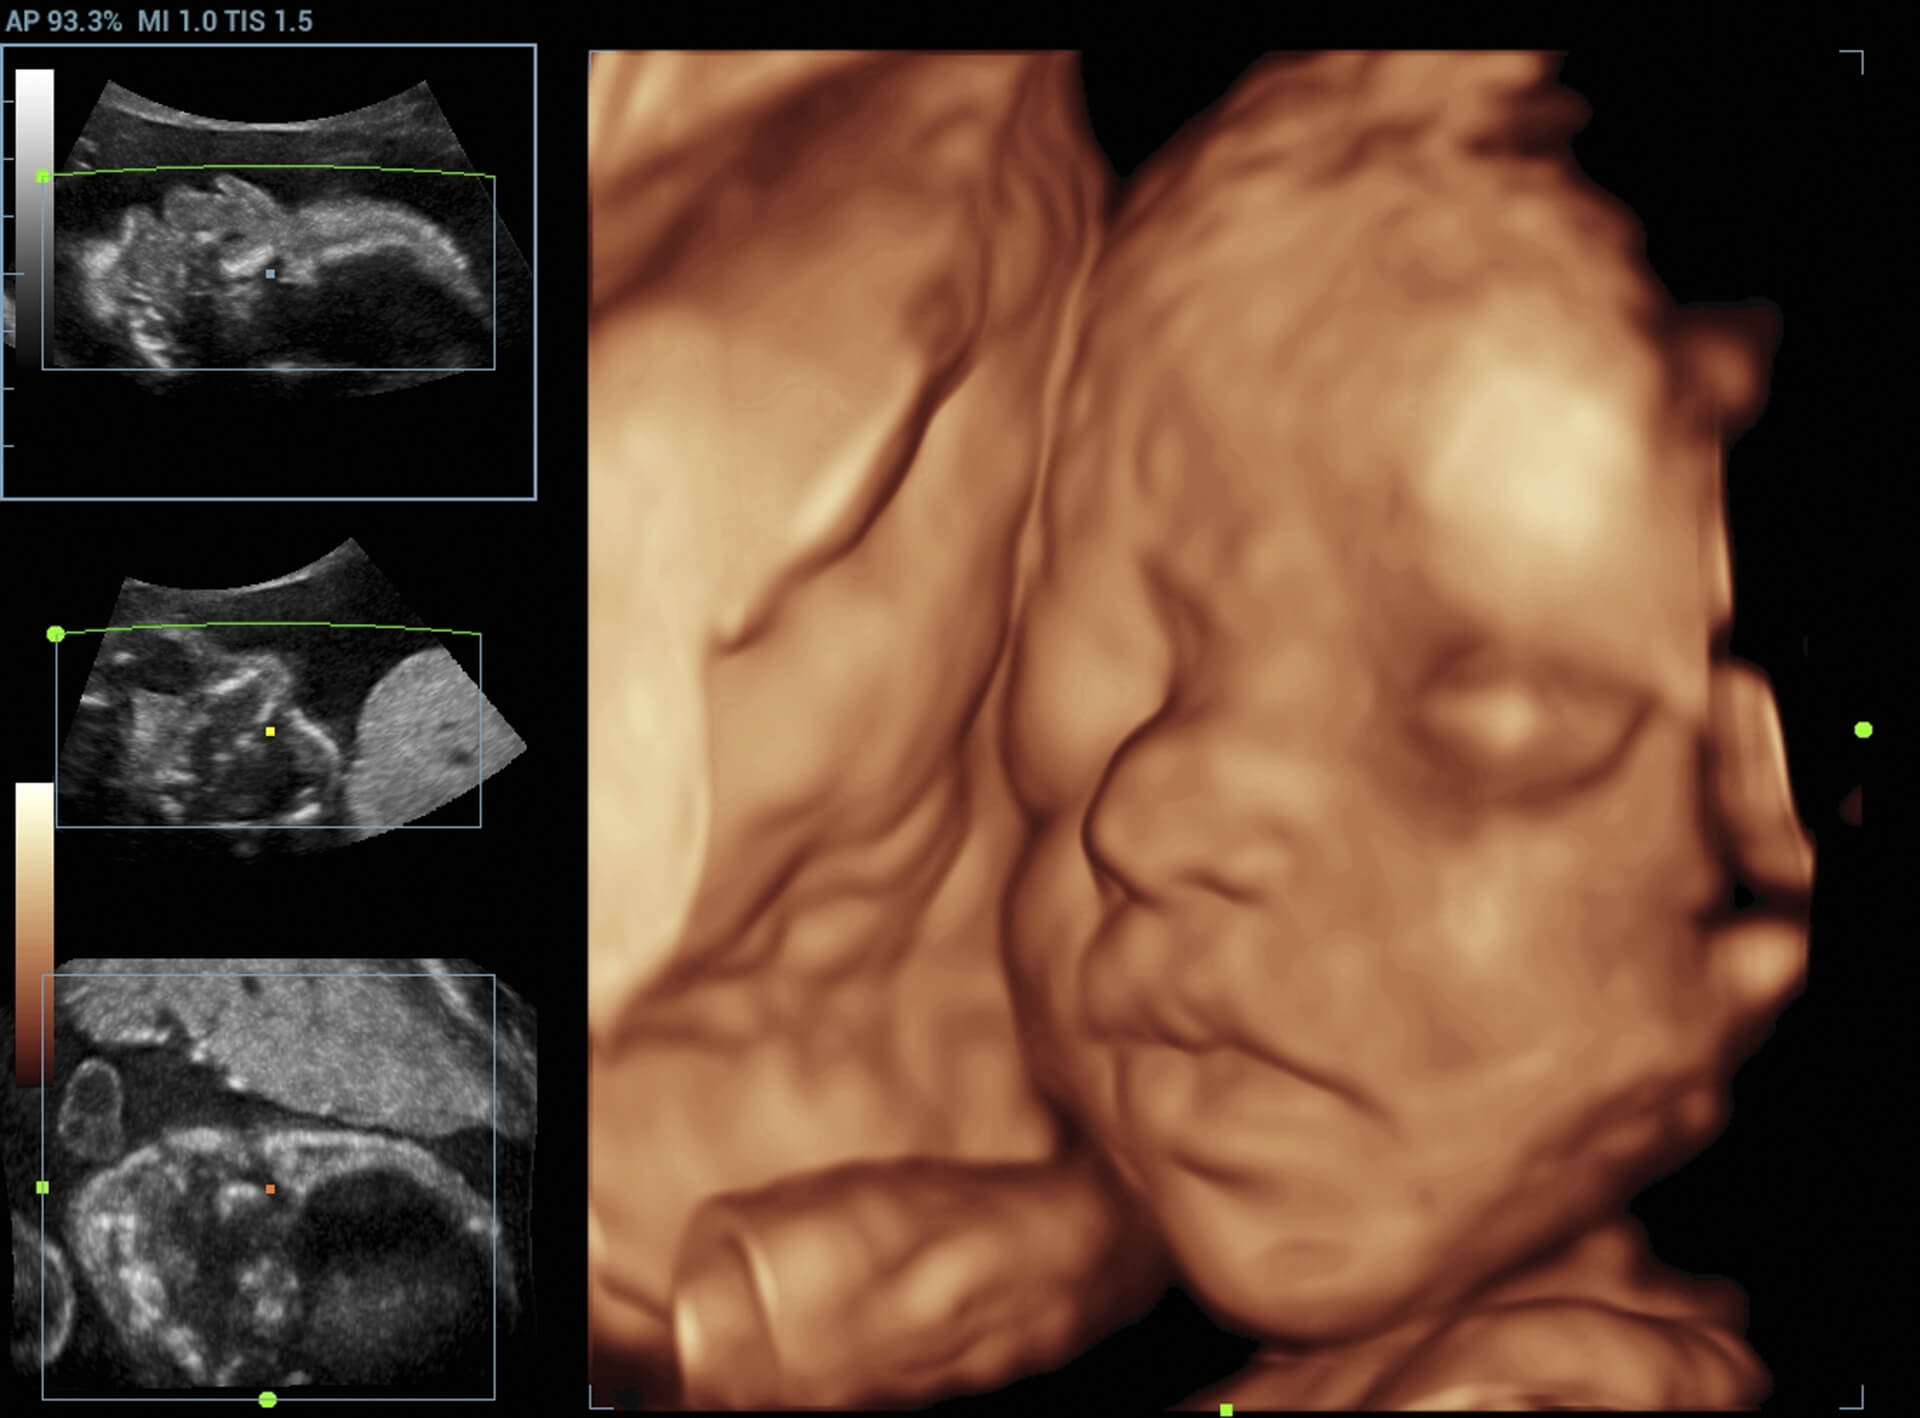

Understanding the Challenges of a High Risk Pregnancy

reading-about-pregnancy-experience

Pregnancy is a time of excitement and anticipation for many women, but for some, it can also be a time of worry and concern. “High-risk pregnancy refers to a pregnancy that is more likely to result in complications due to medical or obstetrical conditions. These conditions can include pre-existing health issues, such as diabetes or … Read more